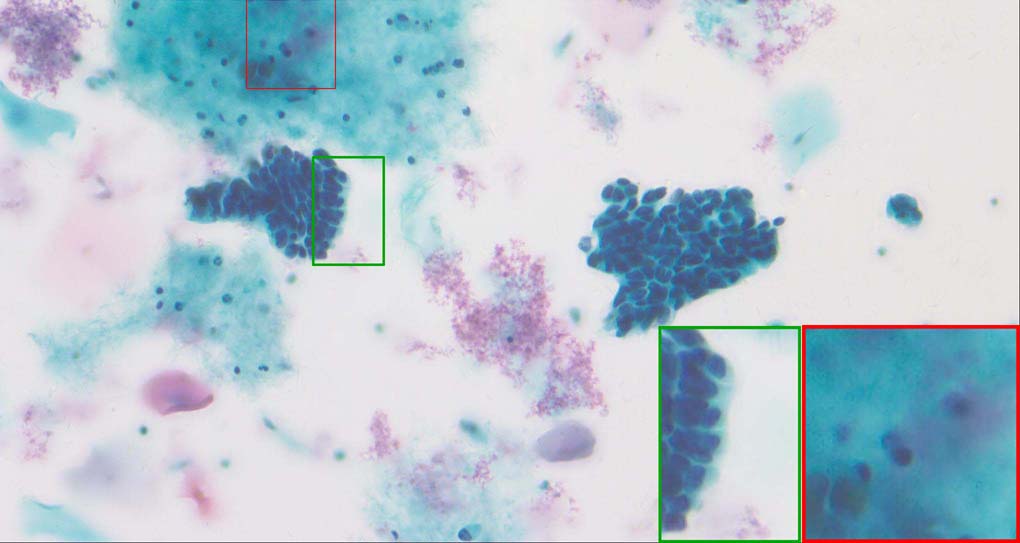

A good image fusion method should contain the following properties. First, it preserves both the details of small size objects and the integrity information of large size objects in the fused image, even in the case of the size of the interested objects varying largely in the image. For example, the cervical cell images from the microscope contain both small size isolated cells and large size agglomerates, which are both useful for cervical cytology [5]. Second, it should be efficient enough to handle large-scale data. For instance, it needs to process thousands of fields of view (FoV) in an acceptable time for the whole slide scanning in digital cytopathology [6], which requires to fuse a series of high resolution images captured at each FoV in a very efficient way. Third, it does not produce obvious artifacts. Despite being studied extensively, to our best knowledge, existing fusion methods may not meet these requirements simultaneously.

To demonstrate the effectiveness and efficiency of the proposed image fusion method , we conduct a set of comparative experiments on three image datasets. The first is composed by 8 pairs of multi-modal medical images and the second one contains 15 pairs of multi-focus gray or color natural images. These two datasets are often used in many related papers and some examples are shown in Figure 3(a) and Figure 3(b). The third one is a new multi-focus cervical cell image dataset collected by ourselves, which consists of 15 groups of color images and each group contains a series of multi-focus cervix cell images with size of or , etc. Some source examples are shown in Figure 3(c). Our source code implemented in C++ along with the new multi-focus cervical cell image dataset is available online.

Figure 9, Figure 10 and Figure 11 show the comparative fused results of the multi-focus cell images shown in Figure 3(c). For clarity, we also present a closeup view in the right-bottom of each sub-picture in Figure 9 and Figure 10. As shown in the close-up views of Figure 9, the fused images based on DSIFT, IM, MWGF and BF methods are extremely blurred in the boundary and fail to keep the details of cell nucleus. Furthermore, the DTCWT and NSCT based methods produce halo artifacts in the fused images, while GFF and CNN based methods fail to preserve the small cell nucleus. LP-SR based method nearly works fine which keeps the most of the details of the small size cells, but the integrity of the clustered large size cells is damaged. Fortunately, in our proposed method, the integrity of the clustered large size cells is preserved and most of the isolated small size cells are maintained from the original images, which demonstrates the best visual quality.